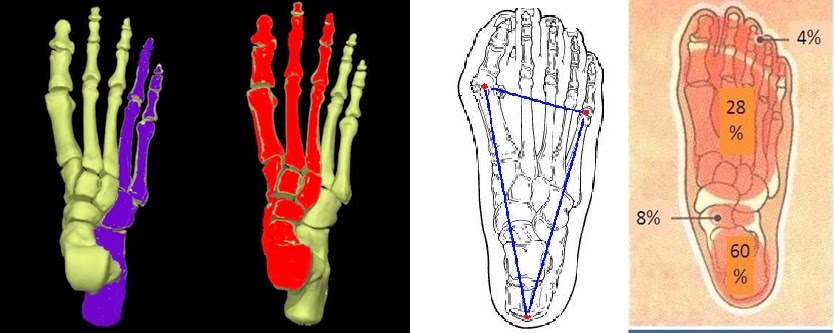

剛開始學走路的小孩都是扁平足, 一直到6、7歲上小學階段,脚會自動修正;但若遲至9歲,仍未改變,則幾可斷言,此童日後一定是扁平足。學理上,腳負重的發展,先是有一相對穩固磐石式的「樁腳」 (如圖1. 藍色部分),其上才是腳的負重「 平台」(如圖2. 紅色部分),平台以浮動的方式,找到它的落點,與磐石(樁腳)鑲嵌成一體,腳負重的結構,於焉定形。至於為什麼「平台」 會向內移行以致 造成扁平足, 原因 可能與發育中的 腳骨骼、 關節 和 韌帶,在力學上三者相互間 的牽扯、角力有關,機制相當複雜。

正常的腳, 落觸地的負重點 呈直角三角形 (如圖3.),這樣的腳,重量的分配 (如圖4.) 最符合力學的經濟原則,久站久走跑跳,省力而不累。 扁平足的腳(如上圖) 負重或行走, 腳會向內傾斜(pronation),重心偏向腳的內緣,承重偏離距骨穹隆,重量則擠向舟狀骨及跟骨,壓在距骨-舟狀骨關節面、 跗骨底部肌腱 或足底筋膜,造成距骨-舟狀骨關節的退化、或跗底肌腱炎 或足底筋膜炎;